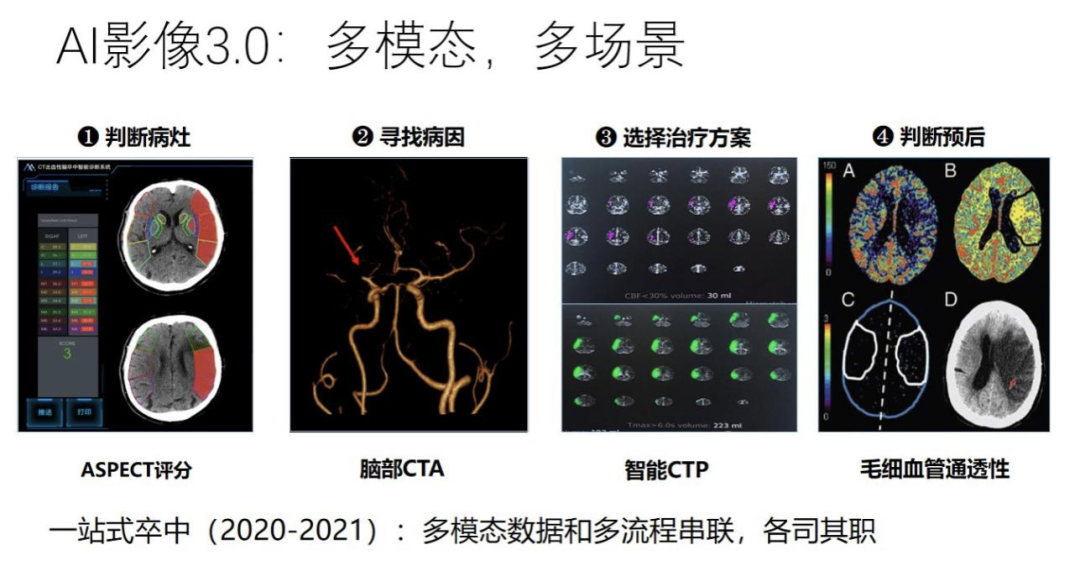

下面我从产品本身如何去迭代和演化的角度做一个简要的介绍。从 2015 年开始,产品从复杂程度、算法和产品设计的过程来看,大概经历了四个阶段,我们称之为 1.0-4.0,从最初 2015 年的单任务单环节,过渡到多任务全流程,再过渡到多模态多场景,到现在的跨模态复合流程。从仅限影像科,到现在进入临床手术,经历了比较大的变化。

到了 3.0 阶段,我们就不仅需要处理单一的场景单一的流程,而是过渡到一个更加复杂的诊断和治疗任务。以脑卒中为例,我们要判断病人是不是脑缺血,第一步首先要做 CT 的平扫,通过 ASPECT 评分大概查看大脑内部有哪个区域可能缺血,当我们知道确实有一些区域有缺血症状之后。下一步需要找到哪一根血管发生堵塞导致缺血,因此要做一个脑部 CTA 来寻找原因。定位原因之后,下一步要确定治疗方案,是打开血管进行手术,还是做保守治疗,因此第三步是做一个更加复杂的脑部 CTP,在一个时间序列内关注脑部所有区域缺血的严重程度,最右边的图中绿色区域就表示比较健康的供血正常区域,红色就表示缺血区域。如果缺血的程度不是很严重,就有可能采取一个比较激进的治疗方案,比如做手术取栓。如果缺血比较严重,那么做手术就可能有危险,因此会采取一个相对保守的治疗方案。可见,对于这样一个比较复杂的病种需要做三个不同阶段的扫描,多模态数据分析和判断过程是串联起来的,每一个模块都有各自的作用。